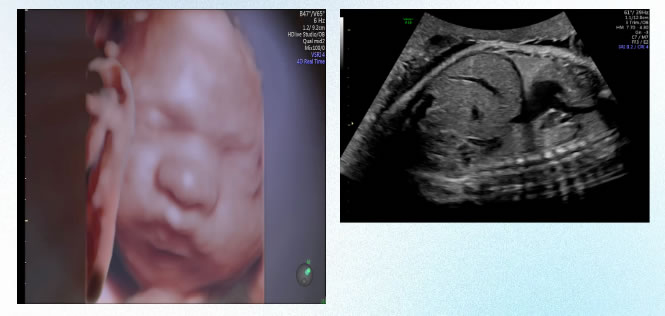

5 IV級超聲(shēng)檢查

在超聲產前篩查基礎上進行針對性產前超聲檢查(產前超聲診斷),是針對胎兒特殊問題進行(háng)特定目的的檢查。

在(zài)學(xué)科帶頭人(rén)左(zuǒ)雲鵬主任的帶領下,超聲科技術力量雄厚,人員素質過硬,開展包括腹部、淺表(biǎo)、婦(fù)產、泌尿、心髒、血管及新生兒顱腦、髖關節等全身各器官的超聲(shēng)檢查項目。其中,胎兒係統篩查、胎兒畸形診斷、胎兒心髒以(yǐ)及新生(shēng)兒顱腦、心髒、髖關節、盆底超聲等(děng)檢查尤具特色,產前診斷水平處於國內領(lǐng)先水平,並率先在本市開展了女性(xìng)盆底、婦科三維、四維(wéi)超聲、子宮(gōng)輸卵管造影等檢查。